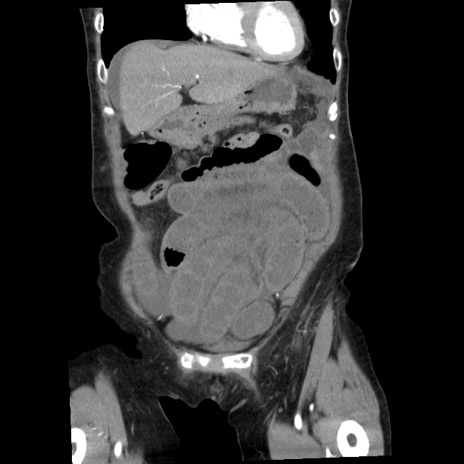

横断像

【症例】80歳代女性

【主訴】腹痛

【現病歴】8時間前から腹痛あり来院。

【既往歴】糖尿病、脂質異常症、子宮体癌にて子宮全摘術

【身体所見】意識清明・会話良好だが腹痛で苦悶様、全腹部にわたって反跳痛と圧痛あり

【データ】WBC 13600、CRP 0.14、LDH 224、CK 90